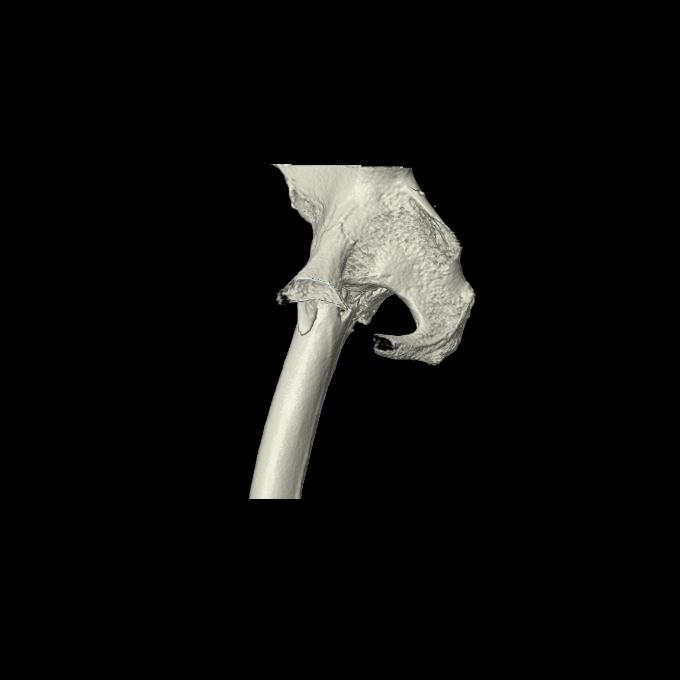

46666 1/28 両股正面+軸と 1/26 右手関節 2R 76歳女性 右転子部骨折

37 1/18 両股正面+軸 1/22 2R 86歳女性 右転子下

82084 1/14 1/20 股関節 2R 78歳男性 右人工骨頭

102811 1/13 股関節 2R 1/19 2R 80歳女性 右DHS

91569 3/25 両股正面とラウエン 70歳女性 人工骨頭+バンクーバー